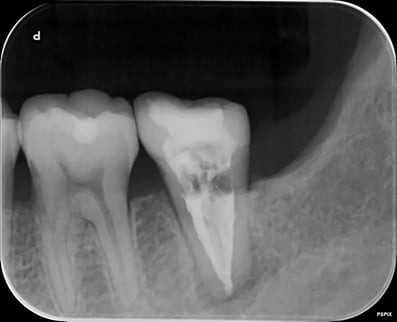

術後5年経過症例。樋状根は抜歯と判断されることが多いようですが、当院ではあきらめずに治療して良い成績を残しています。(7番の近心には、金属修復物下に虫歯があります。他院で定期健診を受けていたようですが、メンテナンスの仕方に問題はなかったでしょうか?)

治療後。根管治療+支台築造+補綴の全てを完結して、根管治療の予後は決定されます。根管治療だけをやって、あとは知らないというやり方は、本当に専門医のやることでしょうか?

約1ケ月後ですが、根の先の炎症の証である透過像は、消失し、噛むと痛いなどという臨床症状も消えました。